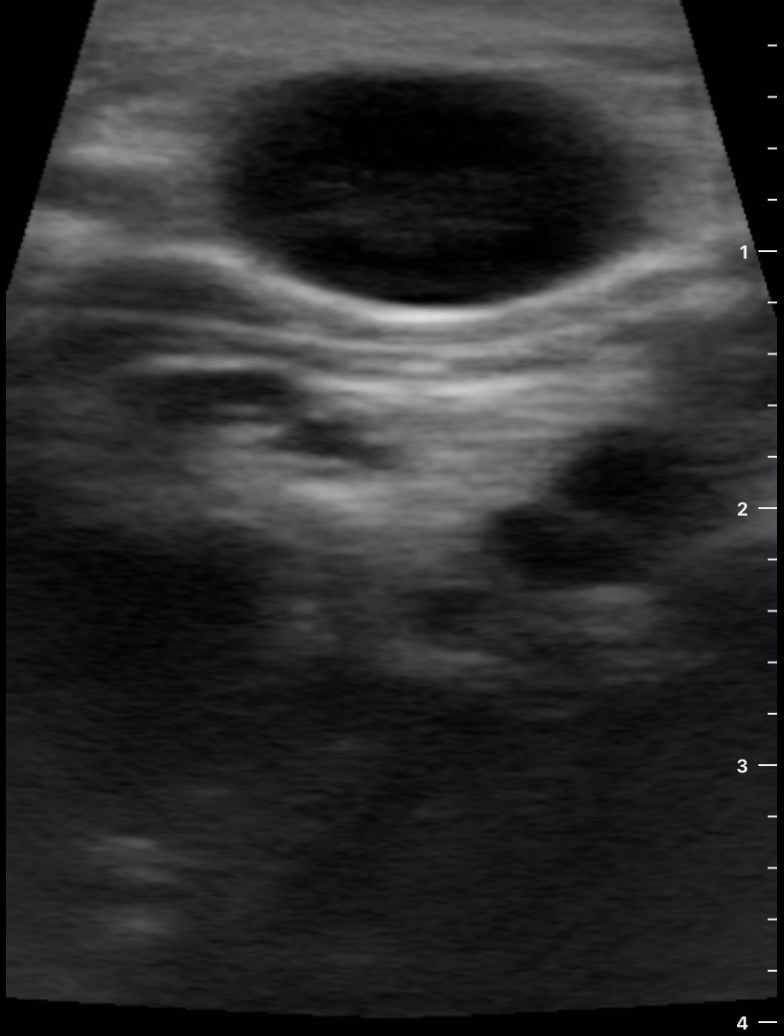

Se decide realizar ecografía clínica con ecógrafo de bolsillo para poder orientar caso, donde se aprecia tumoración de gran tamaño hipoecoica, heterogénea, con calcificaciones de pequeño tamaño en su interior, dependiente de lóbulo tiroideo derecho, sin poder definir límites inferiores, y sin poder localizar la vena cava inferior pero visualizando imagen de vena trombosada junto al istmo.